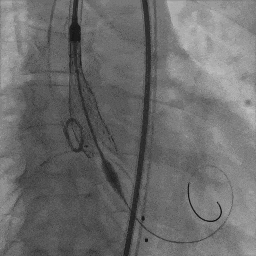

工作体位瓣膜释放

左右窦重合体位造影

患者取平卧位,局麻镇静,颈内静脉置入中心静脉置管,测中心静脉压3cmH2O,左侧桡动脉穿刺置管监测动脉压力。术区无菌消毒铺巾,穿刺右侧桡动脉并置入6F鞘管,超声引导下穿刺双侧股动静脉,右股动脉预置两把Proglide缝合器,左侧股动静脉留置6F鞘管。将Lunderquist加硬导丝送至升主动脉,沿加硬导丝送20F GORE动脉鞘管。将临时起搏漂浮电极经右股静脉送至右室心尖部位,测试起搏器工作良好。予肝素6000单位,ACT大于250s。经左股动脉置入6F猪尾导管,在释放体位下行主动脉根部造影。经右侧桡动脉送脑保护装置分别在左颈总动脉、头臂干动脉释放保护。经右侧股动脉送入6F JL4.0造影导管造影提示:左前降支未见明显狭窄,TIMI血流III级;回旋支未见明显狭窄,TIMI血流III级。送入6F JR4.0造影导管造影提示:右侧冠脉未见明显狭窄,TIMI血流III级。在AL2导管指引下,直头导丝跨瓣至左心室,沿导丝送猪尾导管至左心室,测得跨瓣压差50mmHg。经猪尾导管送入塑形后的加硬导丝送至左心室内,沿加硬导丝送启明L26主动脉瓣系统至主动脉瓣处,在释放体位下释放至工作状态,经猪尾导管行主动脉造影示瓣膜定位良好。继续完全缓慢释放瓣膜。送入20×40mm球囊至主动脉瓣,在180次/分起搏下,收缩压下降至50mmHg时行球囊扩张,扩张无明显腰征。主动脉造影示瓣膜支架膨胀良好,微量瓣周漏。撤出输送系统。经胸超声评估主动脉瓣位为人工瓣回声,位置固定,瓣叶活动良好。主动脉造影提示主动脉无夹层、出血。行造影提示腹主动脉、髂动脉、股总动脉未见明显异常,缓慢撤出20F大鞘管,缝合右侧股动脉穿刺点,保留右侧临时起搏器并固定良好。